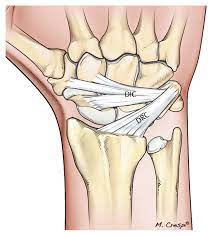

뒤쪽의 경우 Dorsal intercarpal(DIC) 및 Dorsal radiocarpal(DRC) ligament로 구성되어 있습니다.